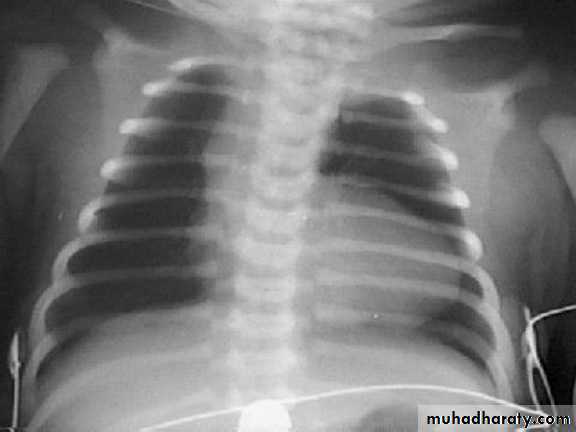

• Cardiomegaly, rib notching on X-ray.

notching of ribs in

coarctation.• Treatment